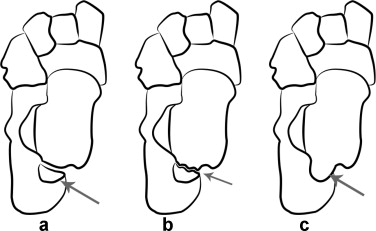

解剖